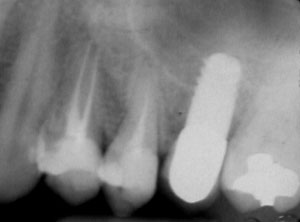

At the time of surgery, local infiltrative anesthesia was administered (lidocaine 2% with epinephrine, 1:100,000). A full-thickness mucoperiosteal flap was raised. The initial osteotomy was performed on midcrestal bone using a rose-headed bur. To prepare the osteotomy site for implant placement, sequential alternating osteotomes with variable conicity were used, drilling 2-mm shorter than the length of the implant to be placed (Figure 3A and Figure 3B). The implants presented initial primary stability (Figure 4), the cover screws were placed, and the implants were submerged for a healing period. The tissue was approximated, and the patient was instructed not to wear any denture or to place pressure on the healing site.

Second-stage surgery was performed after 5 months; healing abutments were placed, and the soft tissue was allowed to heal for an additional 5 weeks. Splinted porcelain-fused-to-metal (PFM) crowns supported by custom gold abutments then were delivered (Figure 5).

Figure 4 Implant positioning; the radiograph taken 4 weeks after placement confirmed good primary stability.